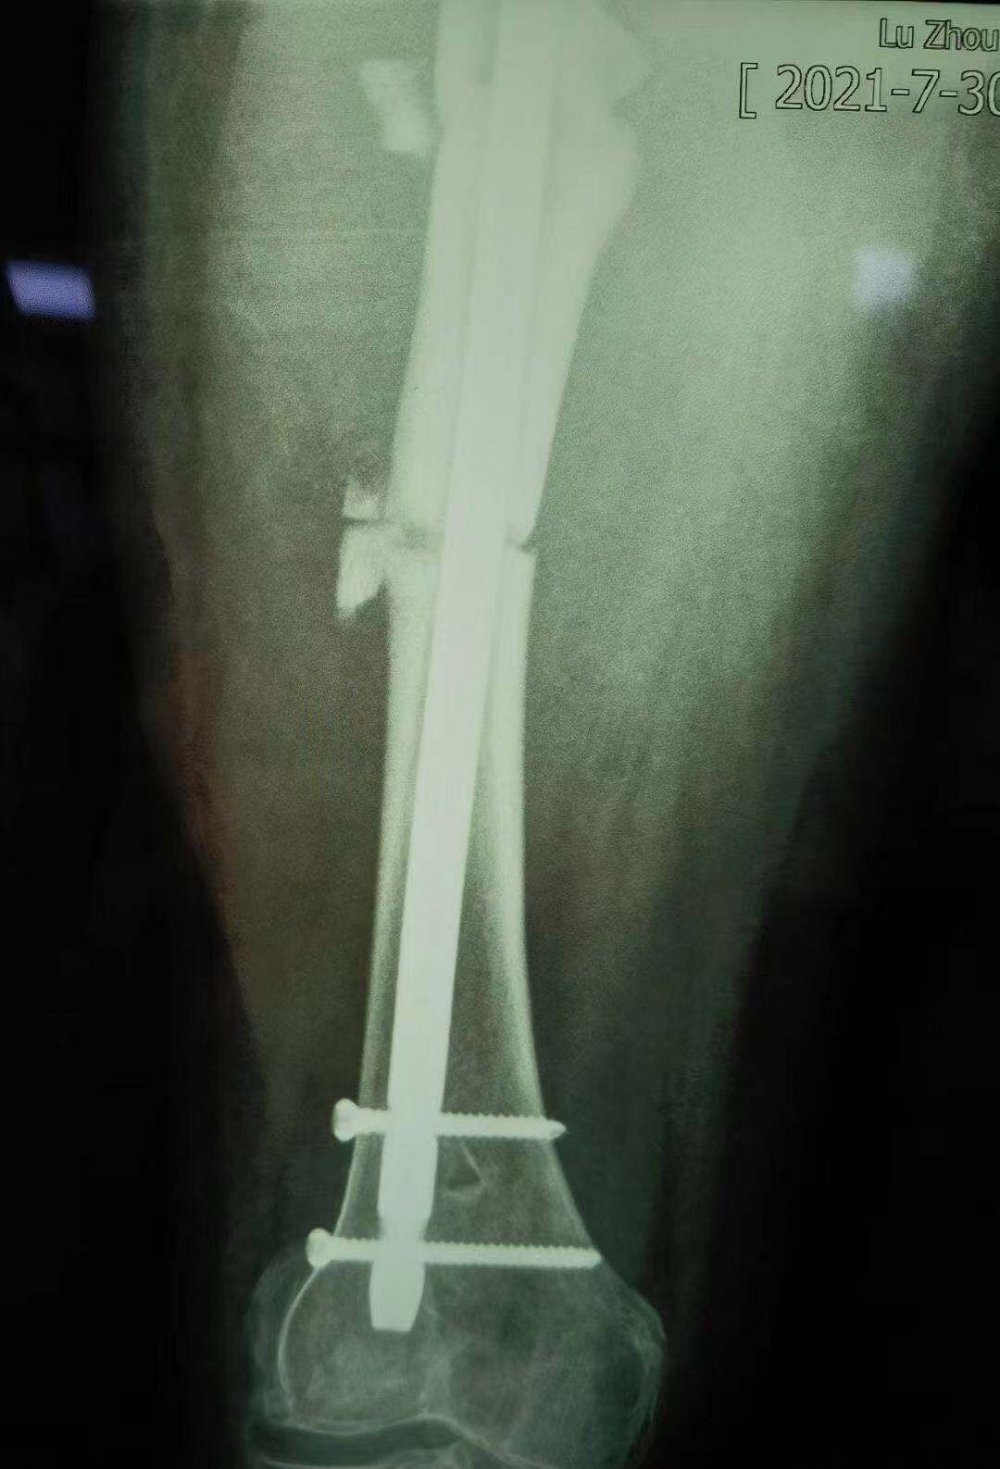

術(shù)后拍攝的X光片

據(jù)汪永泉主任介紹,此次手術(shù)很成功,術(shù)后通過(guò)觀察,病人目前沒(méi)有血管的危象,而且整個(gè)神經(jīng)沒(méi)有牽拉,而且病人整個(gè)下肢體長(zhǎng)度,也基本達(dá)到術(shù)前預(yù)想的恢復(fù)長(zhǎng)度。

但因張女士屬于股骨上段骨折畸形以后手術(shù)歸正,整個(gè)股骨頭的負(fù)重區(qū)已經(jīng)發(fā)生了一些改變,髖關(guān)節(jié)關(guān)節(jié)炎也可能存在,因此張女士還需進(jìn)行后續(xù)的康復(fù)性治療和護(hù)理。